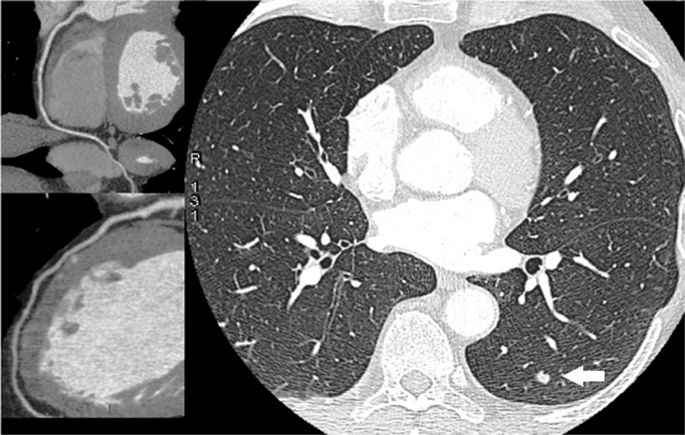

Pulmonary nodules were detected in 7 of the 55 Gr. A subjects who had simultaneous lung and cardiac CT evaluation (Table 4). Three subjects had evidence of solid nodules <6 mm. These nodules were deemed as ‘negative’ on the basis of the NCCN recommendations (Fig. 4). Four cases had solid nodules >6 mm (range: 6–11 mm). In 2 of them, follow-up thorax CT was scheduled. Two patients, conversely, had a complete diagnostic work-up, including positron emission tomography, and eventually underwent surgery (Fig. 5). Lung cancer (adenocarcinoma) was confirmed by histological study after tumor resection in both cases. No pulmonary nodules could be detected in the 55 Gr.B who underwent cardiac CT only.

A case of coronary artery disease and lung cancer detection. CT images of the lungs showed a 20 mm pulmonary nodule (white arrow) in the left lobe (right panel). The patient underwent a complete diagnostic work-up, including positron emission tomography, and eventually underwent surgical resection. The cardiac CT revealed normal left coronary artery and right coronary artery (left panels).